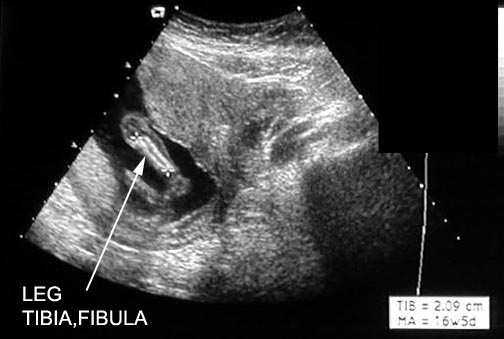

Measurements |